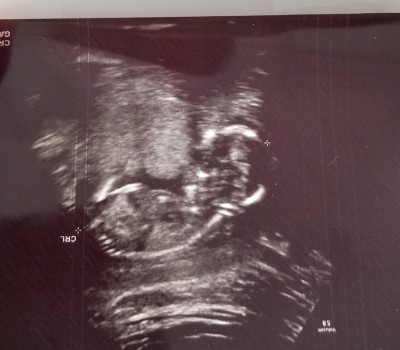

Kızlar bugün gittim kontrole doktor dedi bağdaş kurmuş görünmüyor dedi

Gebelik haftası 14

Bacaklarının arasını kapatmış yani bir sonraki doktor randevusunda açarsa görürsün umarım canım